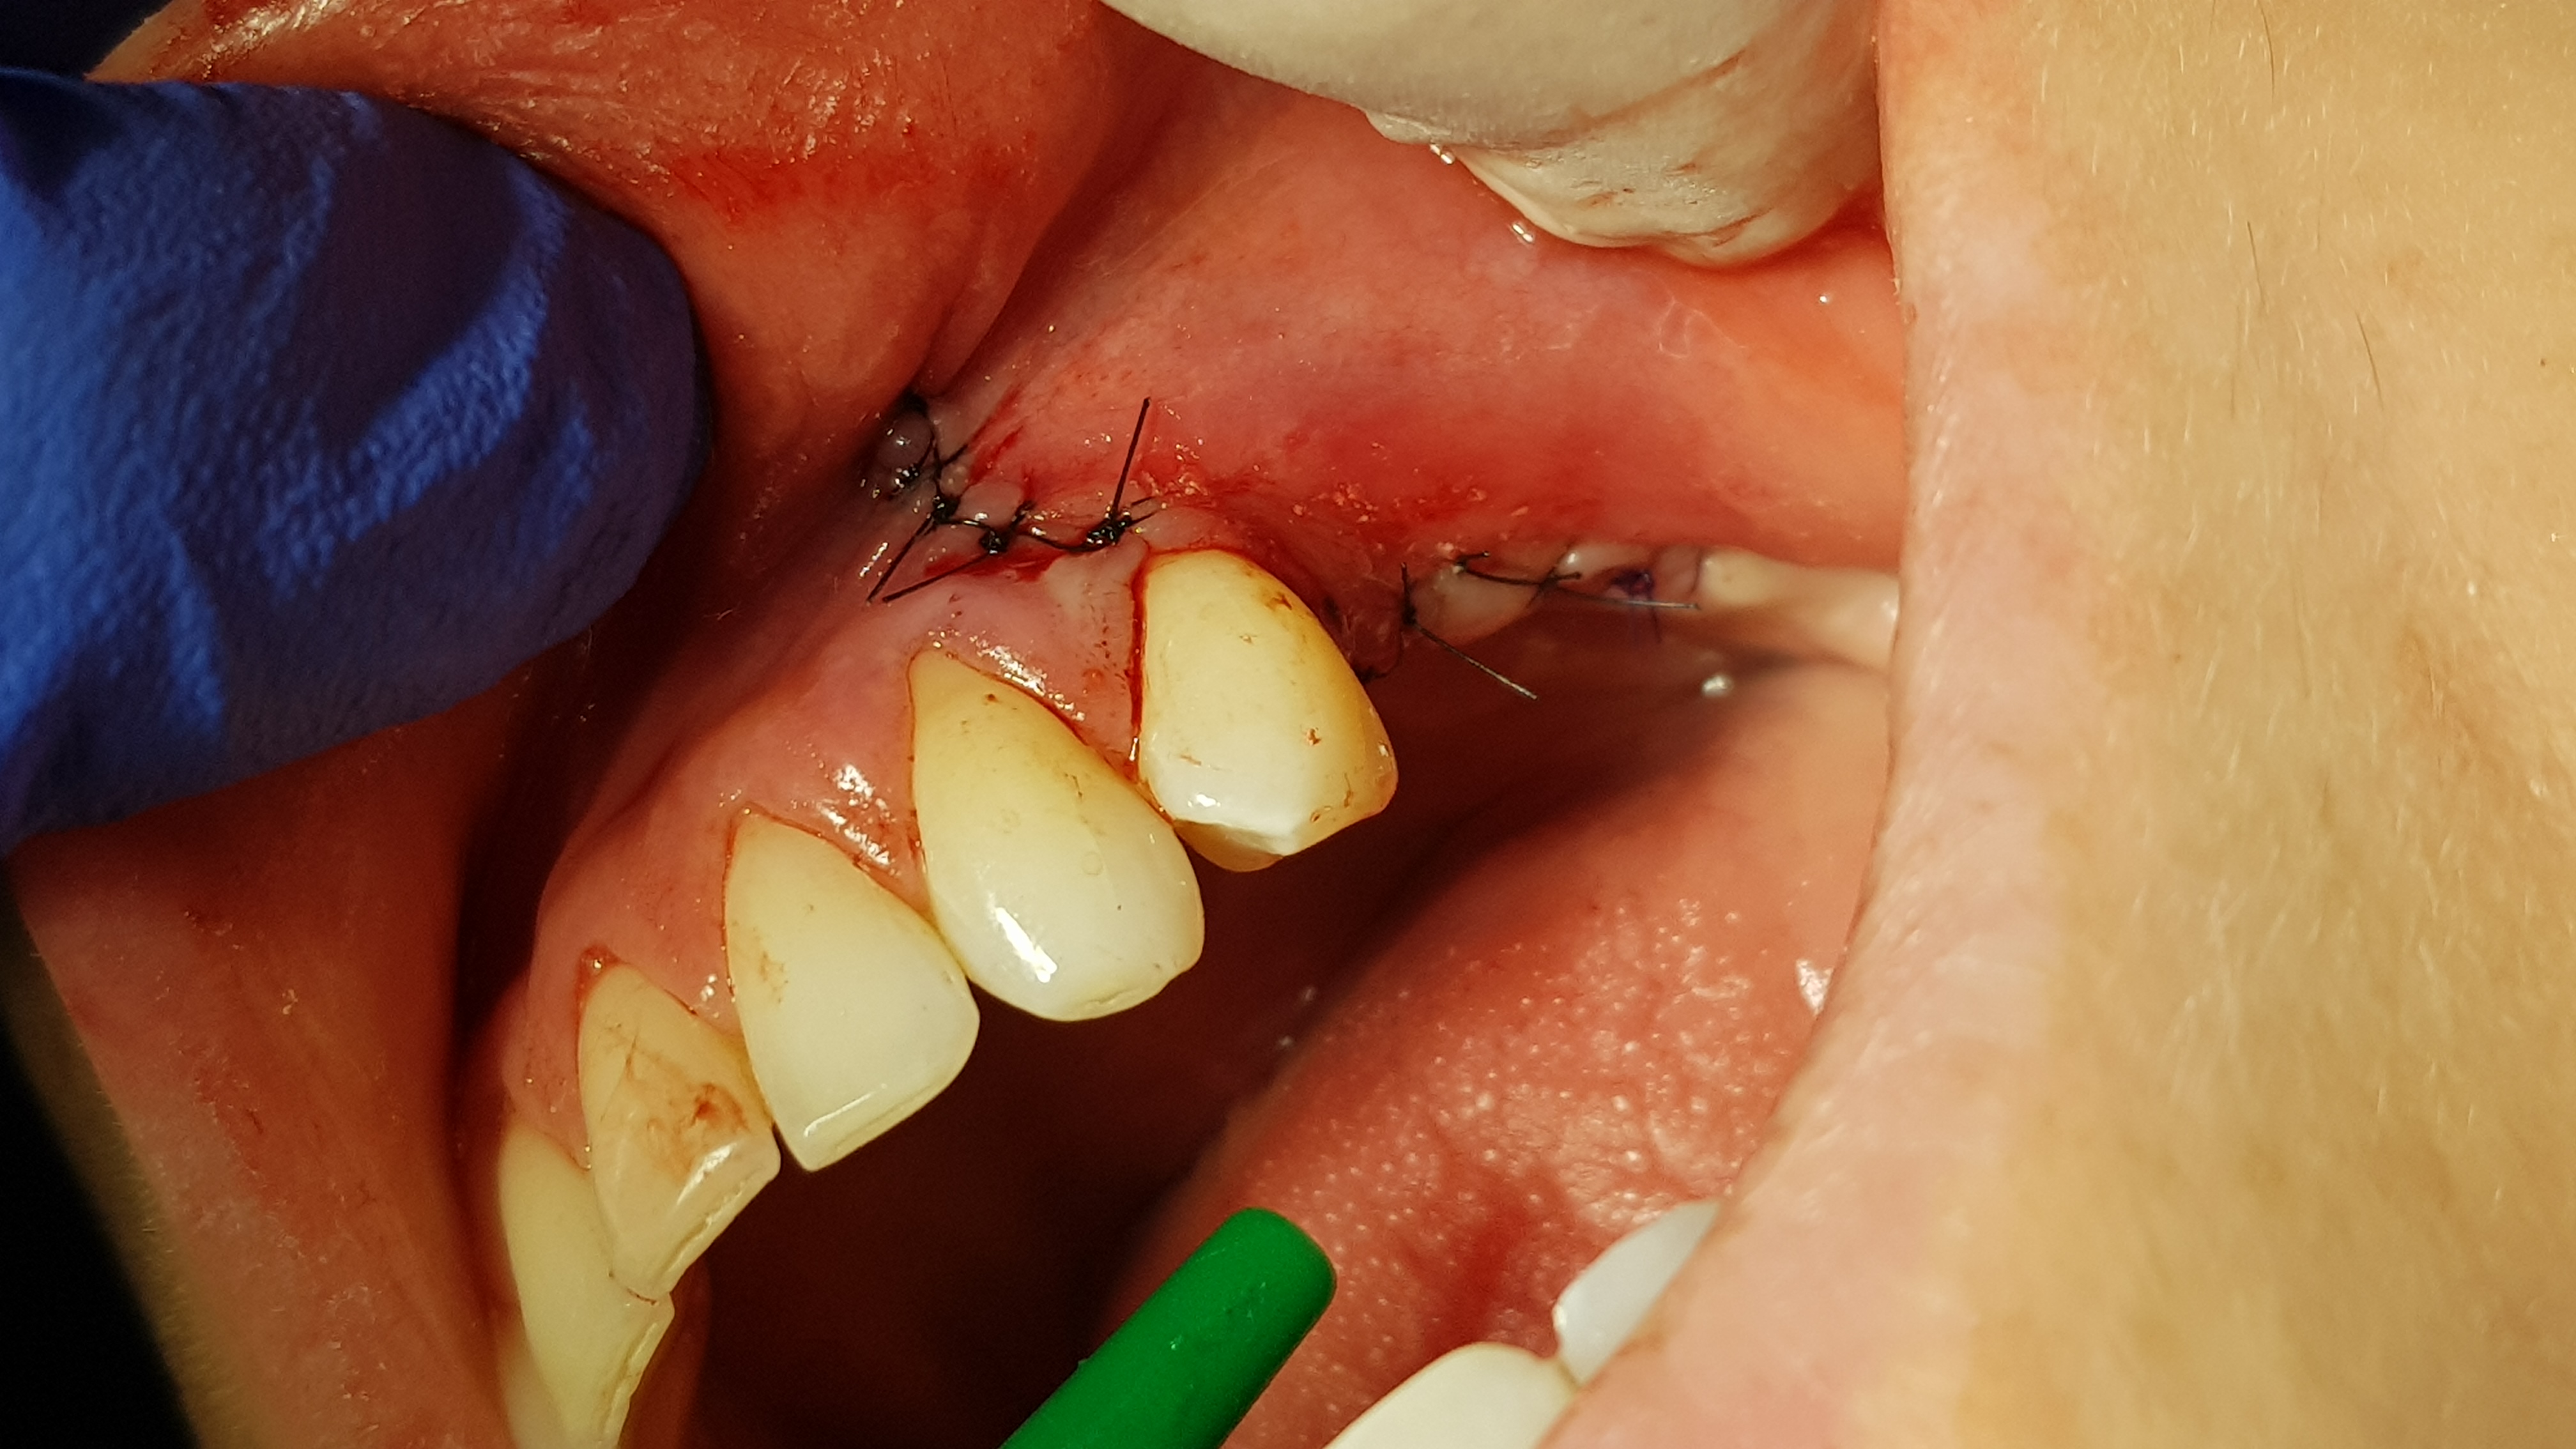

Kształt opracowano ręcznie przy użyciu raspatora i sterylnych gazików 5/5 cm. Następnie ranę przykryto płatem bez podcinania okostnej, a jedynie rozciągając go o kilka milimetrów dzięki wykorzystaniu pewnej elastyczności błony śluzowej. Ranę zaopatrzono szwami (polidioksanon 4-0, igła okrągła kłująca, długość 16 mm, profil ½ koła oraz nylon 5-0, igła odwrotnie tnąca, długość 12 mm, profil 3/8 koła) (ryc. 9). Pacjentka po zabiegu stosowała standardową antybiotykoterapię doustną (Amoksycylina 1.0 g co 12h 7 dni) oraz miejscowo płukanie jamy ustnej roztworem chlorcheksydyny. Rana goiła się prawidłowo, szwy usunięto w 10 dobie po zabiegu oraz wykonano kontrolne projekcje rtg, które wykazały prawidłowe utrzymanie cementu na wyrostku (ryc. 6-12).

Regenerację blaszki przedsionkowej potwierdzono także klinicznie po odwarstwieniu płata podczas zabiegu planowej implantacji. Zmierzono szerokość wyrostka na poziomie 7-8 mm (ryc.14). Po wyrównaniu płaszczyzny wyrostka (ryc. 15) wykonano łoża dla implantów śrubowych w okolicy 45 (dł. 10 mm, śr. 3.7 mm) i 46/47 (dł. 10 mm, śr. 4.1 mm) (ryc.16), które wprowadzono w kość z momentem obrotowym około 25 Ncm. Ranę zaopatrzono szwami (PTFE – politetrafluoroetylen 4-0, igła odwrotnie tnąca, profil 3/8 koła długość 16 mm) (ryc.17).